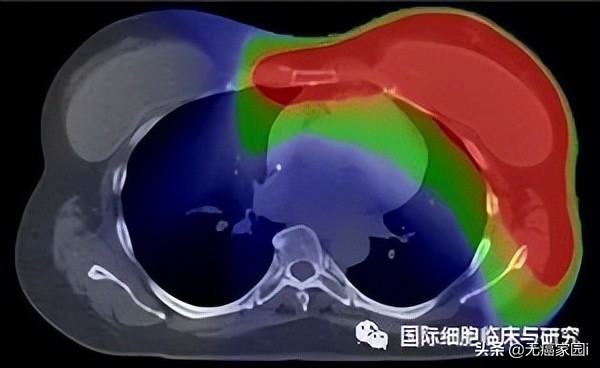

注:红色:高辐射剂量;绿色:中间辐射剂量;蓝色:低辐射剂量

图片依次为质子治疗(上图)和常规X射线疗法(下图)